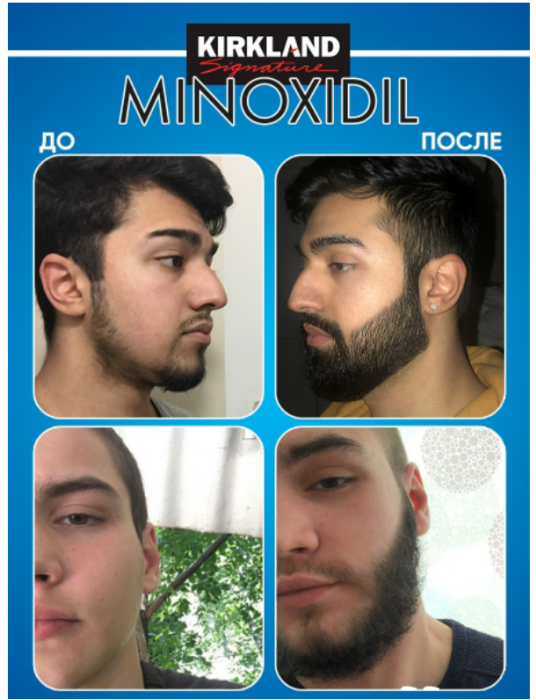

1 590 ₽/шт.0 ₽/шт.

АртикулAS-5278508